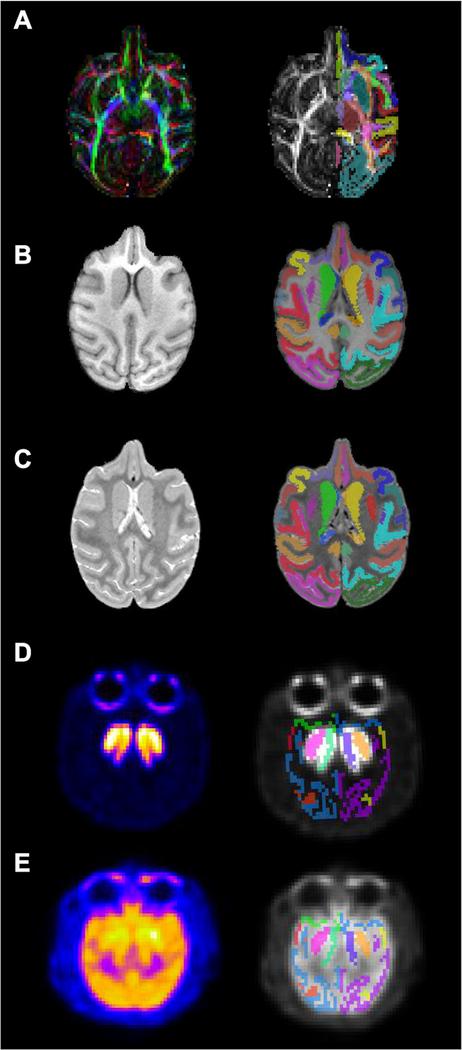

Macaques are the most common nonhuman primate (NHP) species used in neuroscience research. With the advancement of many neuroimaging techniques, new studies are beginning to apply multiple types of in vivo magnetic resonance imaging (MRI), such as structural imaging (sMRI) with T1 and T2 weighted contrasts alongside diffusion weighed (DW) imaging. In studies involving rhesus macaques, this approach can be used to better understand micro-structural changes that occur during development, in various disease states or with normative aging. However, many of the available rhesus brain atlases have been designed for only one imaging modality, making it difficult to consistently define the same brain regions across multiple imaging modalities in the same subject. To address this, we created a brain atlas from 18 adult rhesus macaques that includes co-registered templates constructed from images frequently used to characterize macroscopic brain structure (T2/SPACE and T1/MP-RAGE), and a diffusion tensor imaging (DTI) template. The DTI template was up-sampled from 1 mm isotropic resolution to resolution match to the T1 and T2-weighted images (0.5 mm isotropic), and the parameter maps were derived for FA, AD, RD and MD.The labelmap volumes delineate 57 gray matter regions of interest (ROIs; 36 cortical regions and 21 subcortical structures), as well as 74 white matter tracts. Importantly, the labelmap overlays both the structural and diffusion templates, enabling the same regions to be consistently identified across imaging modalities. A specialized condensed version of the labelmap ROIs are also included to further extend the usefulness of this tool for imaging data with lower spatial resolution, such as functional MRI (fMRI) or positron emission tomography (PET).

猕猴是神经科学研究中最常用的非人类灵长类动物(NHP)物种。随着许多神经影像学技术的进步,新的研究开始应用多种类型的活体磁共振成像(MRI),例如 T1 和 T2 加权对比结构成像(sMRI)以及扩散加权(DW)成像。在涉及恒河猴的研究中,这种方法可用于更好地了解发育过程中、各种疾病状态下或正常衰老过程中发生的微观结构变化。然而,许多现有的恒河猴脑图谱仅针对一种成像方式设计,因此难以在同一研究对象的多种成像方式中始终如一地定义相同的脑区。为了解决这个问题,我们创建了一个来自 18 只成年恒河猴的脑图谱,其中包括来自经常用于描绘宏观大脑结构的图像(T2/SPACE 和 T1/MP-RAGE)的配准模板,以及一个弥散张量成像(DTI)模板。DTI 模板从 1 毫米各向同性分辨率上采样到与 T1 和 T2 加权图像(0.5 毫米各向同性)匹配的分辨率,并为 FA、AD、RD 和 MD 导出了参数图。标签图体积描绘了 57 个灰质感兴趣区(ROI;36 个皮质区和 21 个皮质下结构)以及 74 个白质束。重要的是,标签图叠加在结构和弥散模板上,使得相同的区域可以在不同的成像方式中始终如一地识别。还包括标签图 ROI 的专门浓缩版本,以进一步扩展该工具对具有较低空间分辨率的成像数据(如功能磁共振成像(fMRI)或正电子发射断层扫描(PET))的有用性。